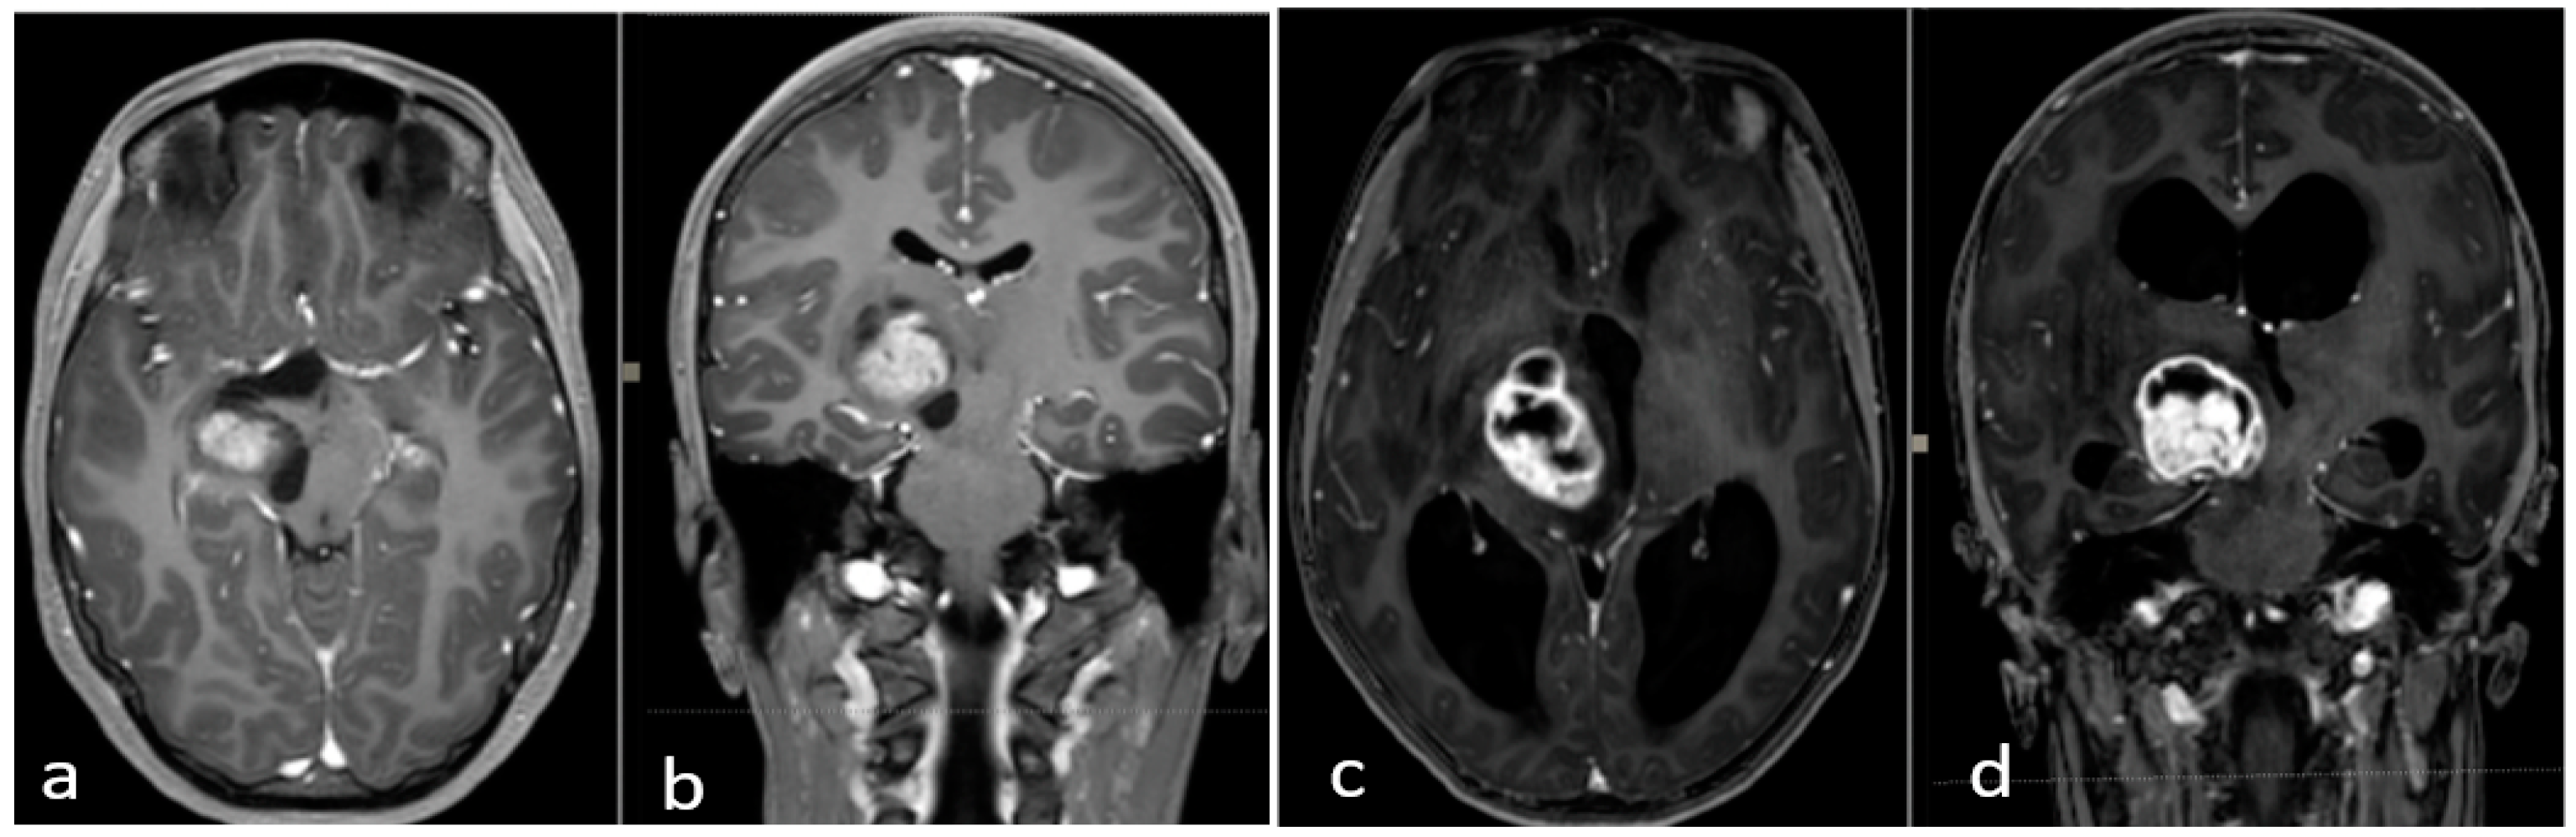

Thalamopeduncular tumors are lesions that arise at the junction between the thalamus and the cerebral peduncles [1] (Figure 4). Most of these tumors are slow-growing pilocytic astrocytoma and displaced the corticospinal bundle, leading to the typical contralateral progressive spastic hemiparesis described as “childhood thalamopeduncular syndrome” [11].

Figure 4.

Preoperative brain MRI of the thalamopeduncular tumor of Case A (a,b) and of Case B (c,d). (a,b) Brain MRI, T1-weighted with gadolinium, showing solid-cystic right thalamopeduncular tumors in the axial plane (on the left) and coronal plane (on the right) in Case A. (c,d) Brain MRI, T1-weighted with gadolinium, showing a right thalamopeduncular lesion with disomogenous contrast enhancement in the axial (on the left) and coronal (on the right) plane in Case B.

Even a subtotal resection offers a good long-term outcome, as shown in our series. Five cases with subtotal resection were clinically and radiologically stable at long-term follow-up (Figure 5).

Figure 5.

(a–d) Brain MRI, T1-weighted with gadolinium. Last follow-up of Case A (a,b) and Case B (c,d). (a,b) Brain MRI, T1-weighted with gadolinium, in the axial and coronal planes of Case A, showing good control of the disease (2021). (b–d): MRI, T1-weighted with gadolinium, in the coronal and axial planes of Case B, showing no evidence of relapse five years post-op.